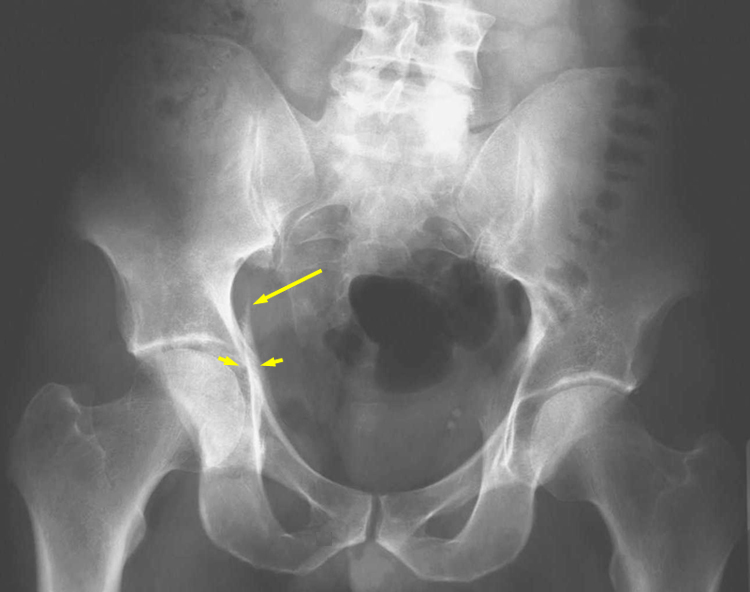

Thomas aquinas high school a roman catholic co educational college preparatory school has acquired national recognition for academic and athletic excellence. Posterior venous plexus injury in pelvic fractures can account for majority of blood loss. Corona mortis latin for crown of death is a common variant vascular anastomosis between the external iliac artery or deep inferior epigastric artery with the obturator arteryit is reported to be present in a third of patients on routine multi detector ct examination 14.

Laceration of corona mortis in 10 15. Knowledge of this variant vascular anastomosis is critical for surgical planning and in pelvic trauma as it is. 82 34954251 l 2 b select answer to see preferred response.

Connection between inferior epigastric branch of the external iliac vessls and the obturator vessels. Exposed and retracted early in the exposure. Lateral in comparision to tibial division most commonly injured neural structure during tha.